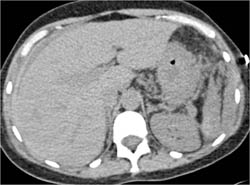

Diagnosis

Focal Nodular Hyperplasia (FNH)